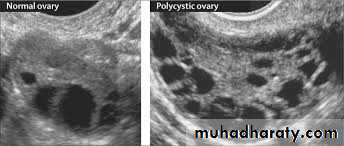

Oligomenorrhea, hirsutism, infertility, and sometimes obesity may appear in young women secondary to excessive production of androgens by multiple cystic follicles in the ovaries.The ovaries are usually twice the normal size, gray-white with a smooth outer surface,& studded with subcortical cysts 0.5 to 1.5 cm in diameter.

Microscopically, there is a thickened, fibrotic tunica with underlying follicular cysts. Stigmata of previous ovulation are usually absent (corpora lutea or albicans).